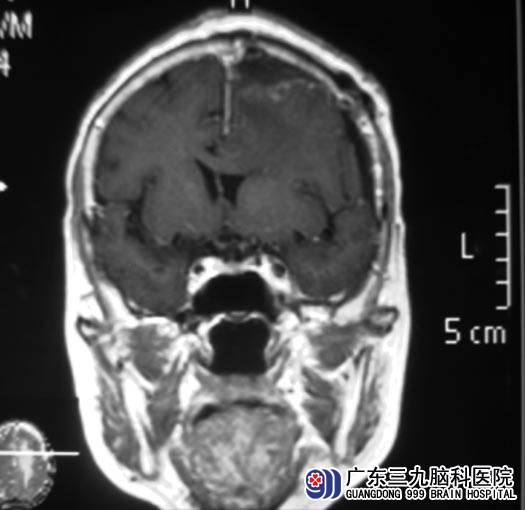

6月8日,广东三九脑科医院综合神经外科 鲁明主任主刀,在全麻下行左侧额部镰旁脑膜瘤切除术,术中见肿瘤位于硬膜下靠近大脑镰旁,呈灰黄色,质韧,血供丰富,边界清楚,先沿肿瘤内侧靠近大脑镰完全分离,再棉片保护肿瘤外侧脑组织,然后分块切除,最后完全切除肿瘤,手术顺利。手术后,肖婆婆头痛、恶心症状基本消失,没有出现任何并发症,可以自行下床活动。术后病理证实为:脑膜瘤(上皮型,WHO I级)。

▲手术后